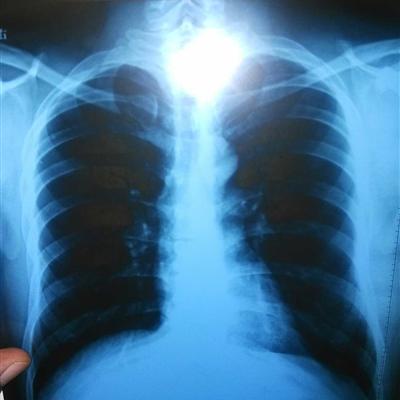

First: lung cancer chest pain is one of the symptoms of lung cancer, but what are the common symptoms of lung cancer in the elderly: breast swelling and pain, phlegm blood tumor inflammation necrosis, capillary damage will have a small number of bleeding, the early performance of lung cancer is usually mixed with sputum. Cough, low fever, can be lung cancer patients in half a month before surgery, in addition to three meals a day, but also add elements diet.

Second: the elderly patients with lung cancer will have no obvious reason for hoarseness with asthma, obvious swelling of one side of the neck, sometimes small eye fission, ptosis, pupil narrowing and other symptoms, can appear when the lung symptoms are not obvious.

Third: the symptoms of early lung cancer is not obvious, there was no cough before, recently cough, long-term treatment can not be cured, and sputum with blood, is a sign of early lung cancer, elderly patients with chronic bronchitis cough for a long time, but the recent cough voice or nature changes, all suggest that there may be canceration.